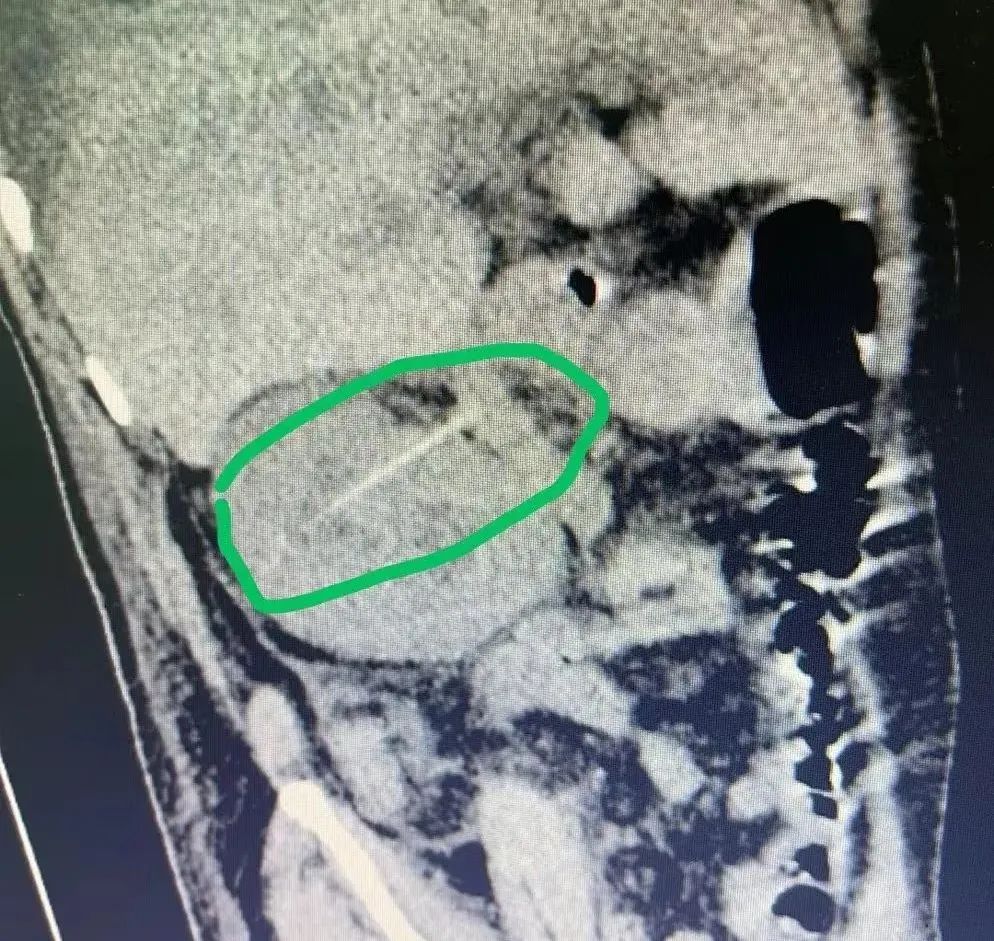

患者张先生(化名)因反复高热、解血尿及血便10余天由外院转入我院治疗。入院时患者高烧不退,上腹部持续性绞痛,阵发性加剧。为查明原因,接诊医生立即为患者进行了腹腔及盆腔增强CT检查,发现一根尖锐的细条样物横在了张某十二指肠降部和右肾之间。

由于发病时间较长、失血过多、感染严重,患者逐渐陷入昏迷状态。时间就是生命,为了挽救患者,医务部立即组织普通外科、泌尿外科、全科医学科、呼吸科、消化科、肾内科、医学影像科等多科专家召开多学科联合会议。经过专家们详细讨论,迅速达成共识,最佳的治疗方案为:立即进行剖腹探查,并决定并由经验丰富、技术精湛的普通外科一区主任黄恒艺团队为张先生手术治疗。手术中进入腹腔后见腹腔肝肾隐窝内有大约100ml的黄色液体,肠管扩张积液并与周围严重粘连,十二指肠降部与右肾粘连水肿,边界不清。专家团队们凭借娴熟的手术技能和多年的临床经验,细致耐心地分离腹腔脏器的粘连,终于发现导致患者生命垂危的罪魁祸首——一根牙签!它竟穿出十二指肠穿入右肾!